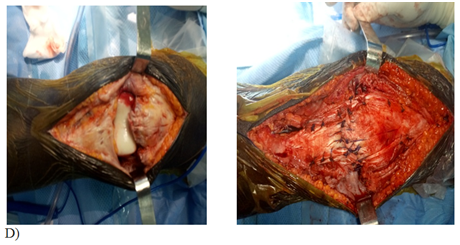

Figure 1 Case: Patient 28 years old male, 10 day history of sports injury with complete patella tear accident: we proceeded to a repair using trans-osseous patella suturing with vicryl 2 and reinforcement semitendinosus.

D- per-operative image.